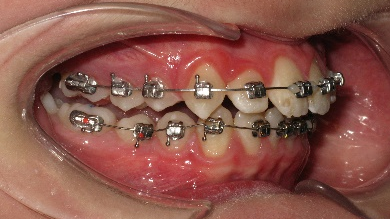

В полости рта: смыкание первых моляров по дистальному типу. Сужение зубных рядов в боковых отделах. 13 и 23 - вестибулярное и супраположение с дефицитом места в зубном ряду на величину ширины коронки клыка. Глубокая резцовая окклюзия.(рис.2.)

Рис.2.Смыкание зубных рядов пациента А. до лечения и окклюзионный вид.